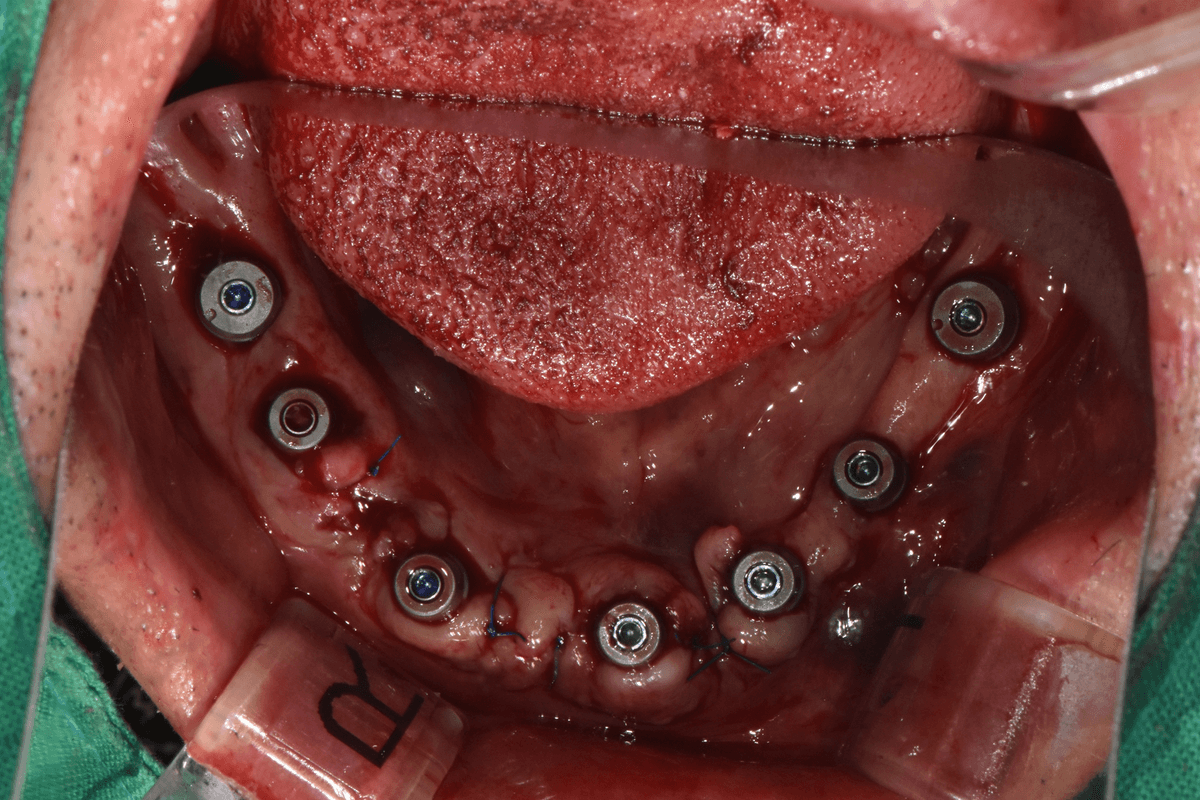

교정 치료 전후 사례

교정과 전문의가 직접 진료한

실제 환자 케이스입니다

이●● · 심한 부정교합